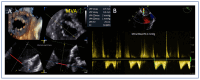

Mitral regurgitation (MR) is a common valvular heart disease associated with significant morbidity and mortality. For patients at high or prohibitive surgical risk, mitral transcatheter edge-to-edge repair (M-TEER) offers a less invasive alternative to surgery. This review outlines key aspects of patient selection and procedural planning for M-TEER, with a focus on clinical and echocardiographic criteria essential for success. Comprehensive imaging-especially 2D and 3D transesophageal echocardiography-is critical to assess leaflet anatomy, coaptation geometry, and mitral valve area. Selection criteria differ between primary and secondary MR and are guided by trials such as COAPT and MITRA-FR. Optimal outcomes rely on careful screening, anatomical suitability, and multidisciplinary evaluation. With growing experience and advancing technology, M-TEER has become a transformative option for treating severe MR in non-surgical candidates.